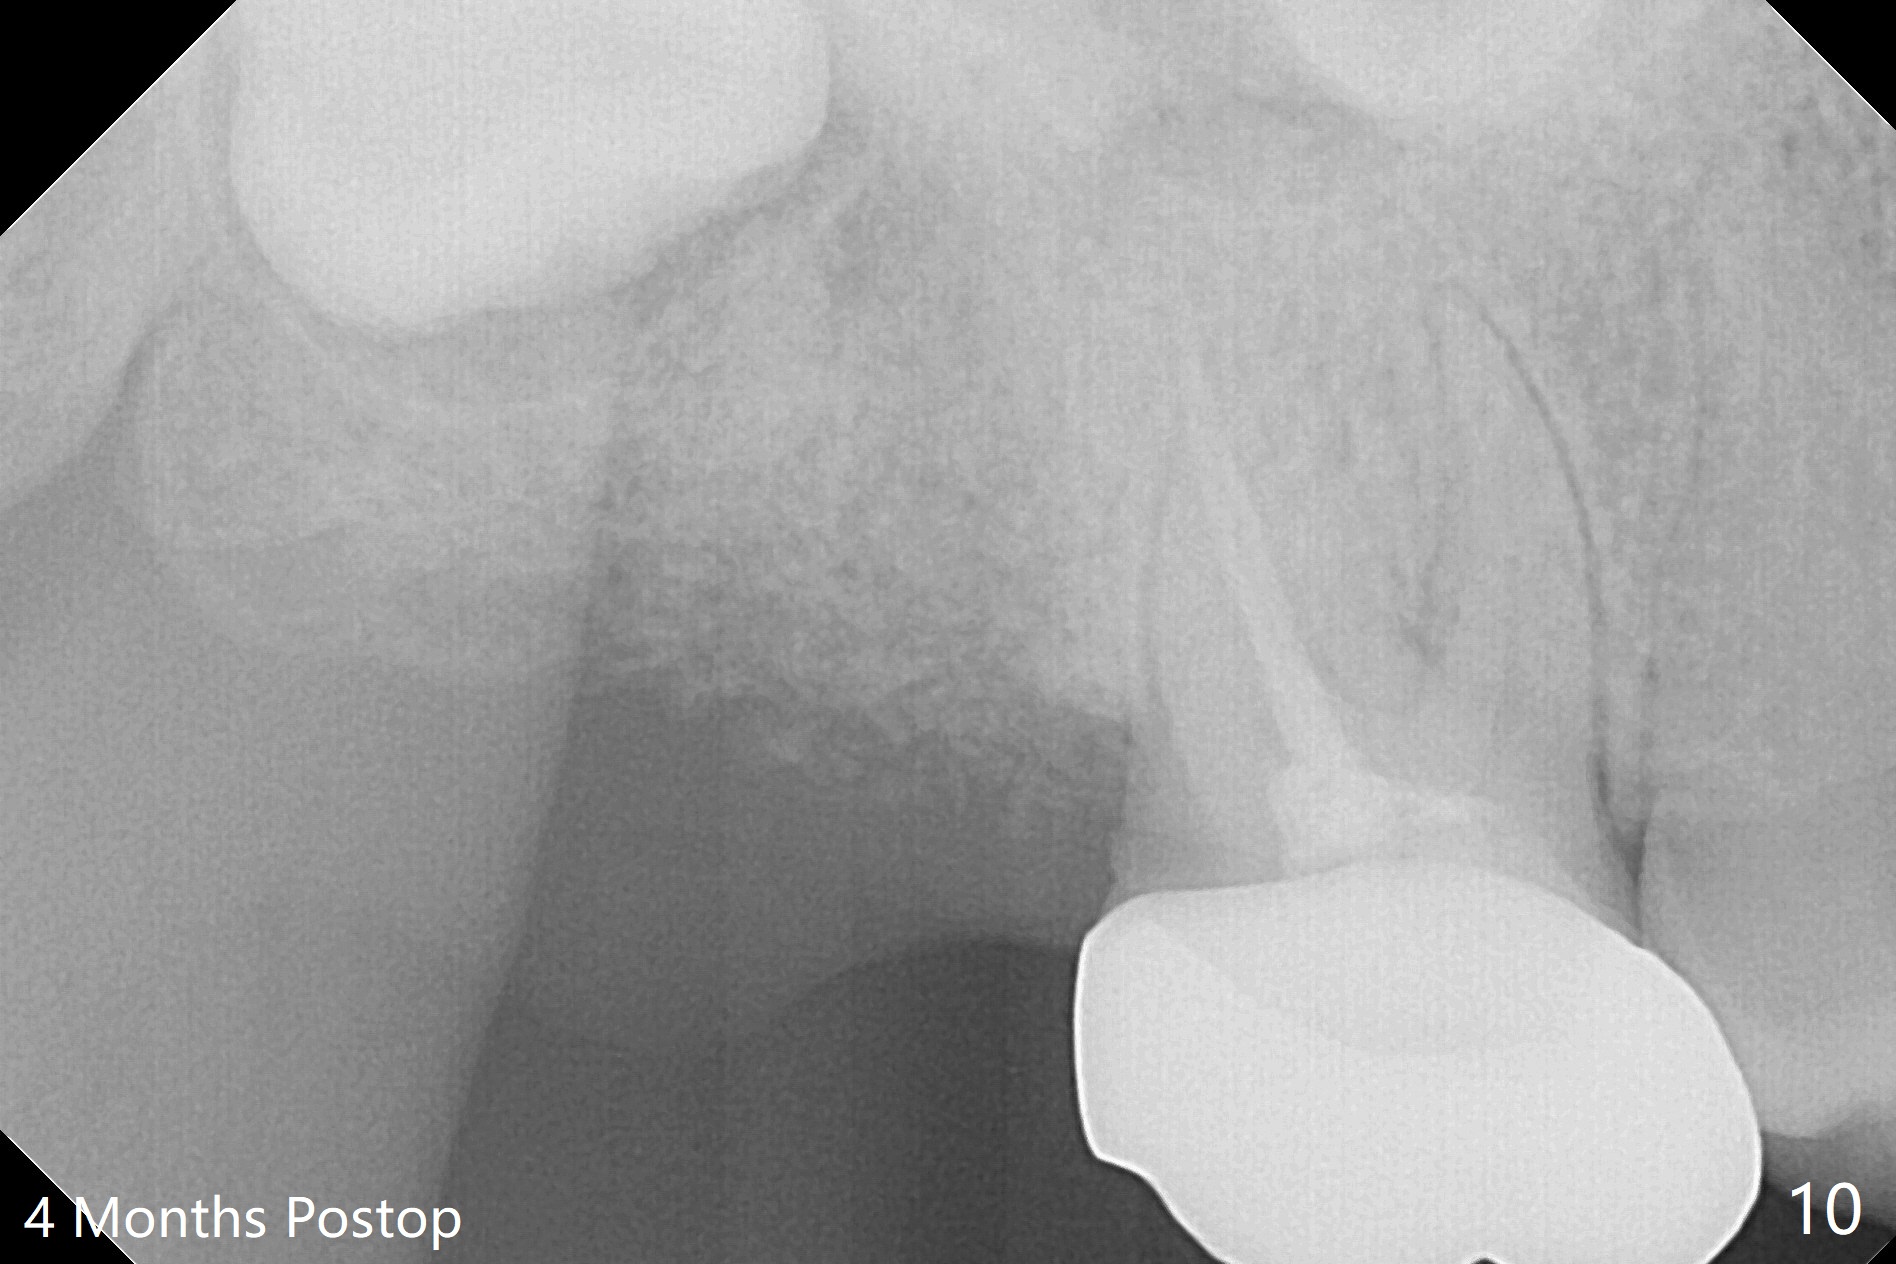

The socket of #2 heals 13 days postop; it appears that the bone graft remains in place (Fig.7,8 *). The patient is instructed to return in 3-4 months for impression and CT for guide. The socket heals 4 months postop (Fig.9,10). She plans to have implant next year, since she wants to add another insurance. The patient returns for implant without removal of the third molar 2 years 4 months post socket preservation (Fig.11). A 5x7.3 mm implant can be placed without invading the sac of the impacted third molar (Fig.12). In fact the lab has a better plan. A lump of bone forms in the previous socket 1 year 4 months postop (Fig.13 *). The ridge is wide and dense (Fig.14). A narrow implant placed oblique could be longer (Fig.15), as compared to a wide, short one (Fig.12).